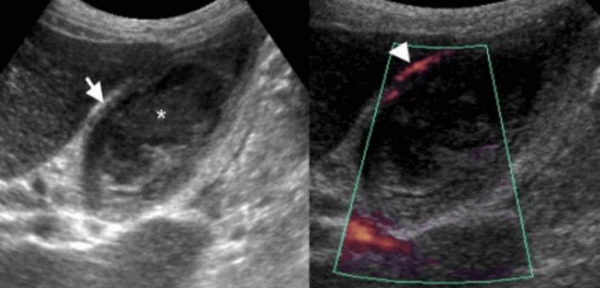

УЗИ некалькулезный холецистит.

74 — летнему мужчине выполнено УЗИ желчного пузыря. Диагноз: острый некалькулезный холецистит. На левой сонограмме стрелкой указано утолщение стенок желчного пузыря. В просвете желчного пузыря взвесь. На правой сонограмме у того же пациента при исследовании в доплеровском режиме выявлен еще один признак воспаления — гиперемия.

Представлен больной с хроническими болями в правом подреберье, который ежедневно воздерживался от еды с вечера. Утолщение слабо выраженное и не является физиологическим. Также визуализируются обструкция и камень. После УЗИ данному больному был поставлен диагноз — хронический холецистит.